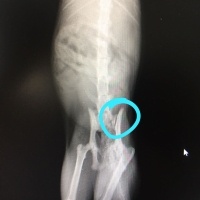

Ayağı kalçadan kırılmış sokak keisine evde bakım veriyoruz şuan."Hareketini kısıtlayın zamanla iyileşir" dedi iki veteriner. Ek olarak da Felaxa malt vermişler kardeşime. Üzerinde hem "tüy yumağı önleyici" hem de kas kemik destekleyici yazıyor.Ilk defa duyduğumuz bir ürün bu.Duyan kullanan var mı? Biz ona kemik suyu vermeye başladık.Bu maltın bir faydası olur mu? Aşina olan kullanan var mı?